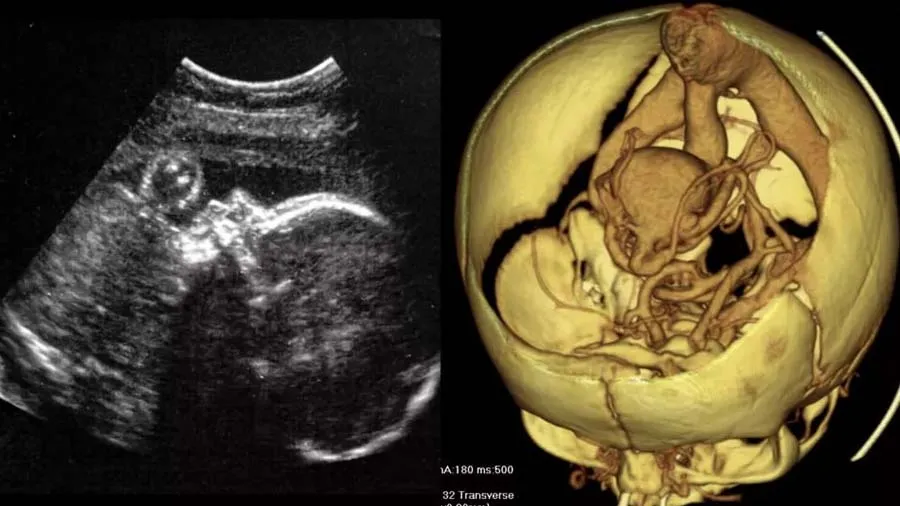

પહેલી વખત ગર્ભમાં કરવામાં આવી ભ્રૂણની બ્રેન સર્જરી, ખતરનાક બીમારીની સફળ સારવાર

મેડિકલ સાયન્સના ઇતિહાસમાં એ પહેલી વખત થયું છે કે, ડૉક્ટરોએ ગર્ભમાં ઉછરી રહેલા ભ્રૂણની સર્જરી કરી હોય. આ સર્જરી પૂરી રીતે સફળ રહી. એમ કરીને ડૉક્ટર્સે બાળકના વિકસિત થઈ રહેલા મસ્તિષ્કમાં ઉછરી રહેલા ઘાતક ડિસઓર્ડરને દૂર કરી દીધો છે. સ્ટ્રોકમાં પ્રકાશિત શોધ મુજબ, આ સર્જરી માટે અલ્ટ્રાસાઉન્ડનો ઉપયોગ કરવામાં આવ્યો. ભ્રૂણનું ઓપરેશન ગર્ભાવસ્થાના 34માં અઠવાડિયામાં કરવામાં આવ્યું. ભ્રૂણમાં ગેલેન મેલાફોર્મેશનની જાણકારી મળી હતી, જે મોટા ભાગે ઘાતક અને આક્રમક હોય છે.

તેમાં મસ્તિષ્કની અંદર ધમનીઓ સામેલ હોય ,છે જે પહેલા કેપિલરીમાંથી પસાર થવાની જગ્યાએ સીધી નસો સાથે જોડાઈ જાય છે. કેપિલરીને ખાસ કરીને બ્લડ પ્રેશરને ધીમું કરવા માટે ડિઝાઇન કરવામાં આવ્યું છે એટલે વિકૃતિનું પરિણામ આવતું ખૂબ મોટું બ્લડ પ્રેશર કેમ કે એ સીધું નસોમાં જાય છે. તેનાથી જન્મ દરમિયાન અને જન્મ બાદ મસ્તિષ્ક અને હૃદયને ઘણો બધો તણાવ થતો અને તેનાથી પાલ્મોનારી હાઇપરટેન્શન, હાર્ટ ફેલિયર અને અન્ય જીવલેણ પરિસ્થિતિઓ ઉત્પન્ન થઈ શકતી હતી.

ગર્ભાવસ્થા દરમિયાન તેની સારવાર કરવામાં આવે છે અને સામાન્ય રીતે ઓડોવસ્કુલર એમ્બોલાઇઝેશન નામની પ્રક્રિયા દ્વારા સારવાર કરવામાં આવે છે. સર્જાનોએ આ પ્રકારની સર્જરી પહેલા પણ કરી હતી, પરંતુ એ પહેલી વખત હતું કે તેને પૂરી રીતે ગર્ભાશયમાં કરવામાં આવ્યું હતું. US ફૂડ એન્ડ ડ્રગ એડમિનિસ્ટ્રેશનની દેખરેખમાં, તેઓ ભ્રૂણના મસ્તિષ્કમાં ઉચ્ચ દબાવવાળા બ્લડ વેસલ્સને બ્લોક કરવામાં સફળ રહ્યા, જેથી જન્મ દરમિયાન દબાવ વધારા રોકી શકાય.